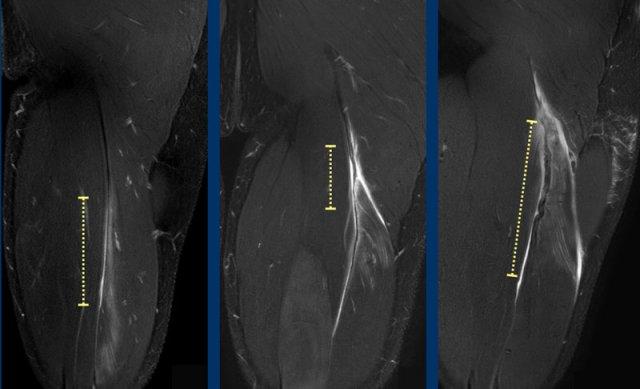

Cả chiều dài vùng phù nề và chiều dài đoạn gân biến dạng đều được đo và ghi nhận trong báo cáo.

Trong trường hợp này, tổn thương gân cơ nhị đầu đùi được phân loại là tổn thương bán phần độ 3, do chiều dài vùng phù nề > 15cm (đường chấm trắng) và chiều dài đoạn gân biến dạng > 5cm (đường chấm vàng).

Thêm hai trường hợp để minh họa cách phân loại này.

A Phù nề cơ 5-10cm (đường chấm trắng) tại vùng MTJ không kèm biến dạng cấu trúc gân, được phân loại là BAMIC 2b.

B Phù nề cơ >15cm (đường chấm trắng), tại vùng MTJ / gân trong cơ, biến dạng gân > 5cm (đường chấm vàng). Gân có hình ảnh gián đoạn với mất tín hiệu thấp trong lòng gân kèm theo dạng gợn sóng, cho thấy mất sức căng khu trú. BAMIC 3b/c.